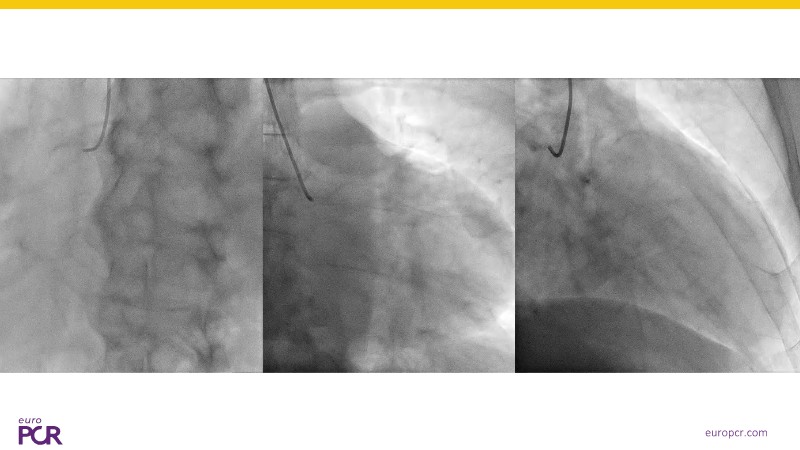

Discover how the next-generation RevoEdge high-pressure cutting balloon is transforming PCI with innovative design and proven clinical outcomes. This session presents a multicenter randomised trial and real-world case discussions, showcasing RevoEdge’s effectiveness in tackling resistant, complex lesions—including long, tortuous, and fibrotic cases. Learn practical tips, tricks, and intravascular imaging insights to optimize lesion preparation and improve patient outcomes. Don’t miss this opportunity to see how RevoEdge helps you cut through challenges and conquer PCI complexities.

- To learn about the clinical benefits and tips and tricks of using RevoEdge high pressure cutting balloon in different types of complex lesions through case-based discussion